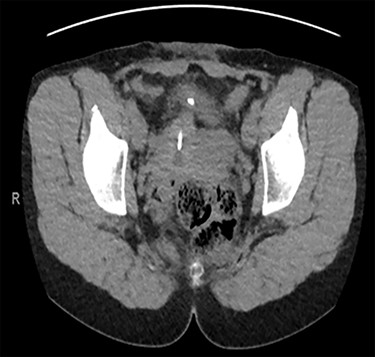

Computed tomography (CT) scan including a urographic phase revealed an IUCD in the vesico-uterine space, with one horn embedded into the bladder (Figs 2–4).

Axial CT urinary tract image demonstrating the device lying between uterus and bladder.